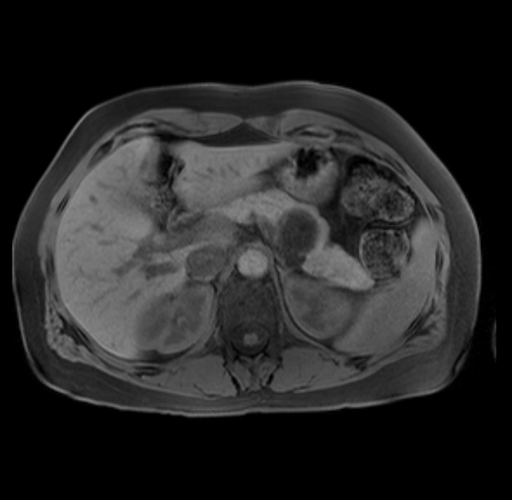

Imaging Analysis

Look through the patient's CT scan to identify any areas of concern for the necessary procedure.

Based on your CT findings, which issue(s) are present and would give reason for "planned slowing down moment(s)" in this case?

Considering a standard distal pancreatectomy procedure, what step(s) of the operation would you do differently in this case?